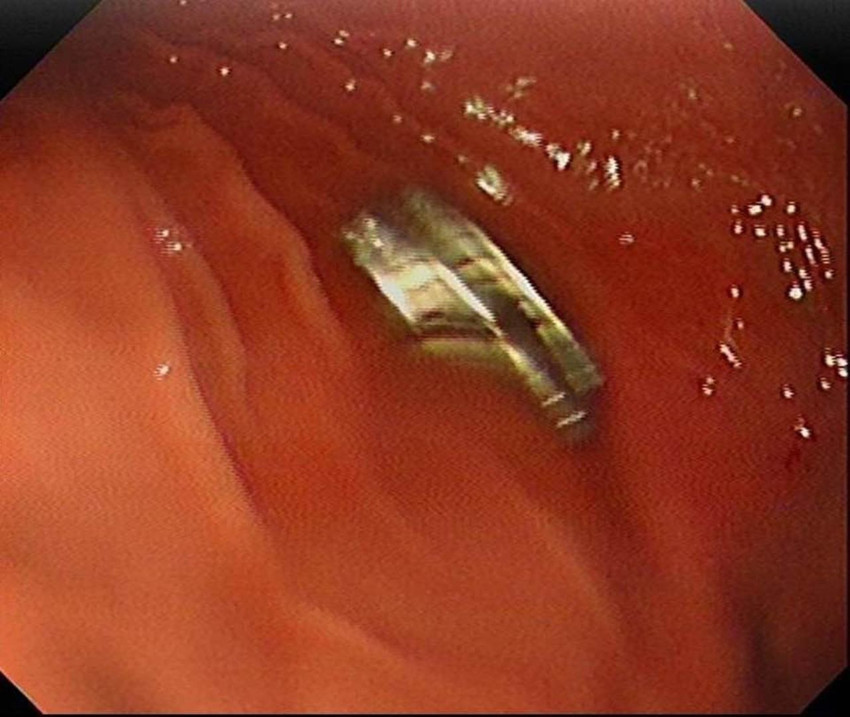

Elazığ’da 3 yaşındaki bir çocuğun yuttuğu 19 mıknatıs, Fırat Üniversitesi Hastanesinde başarılı bir operasyon ile çıkartıldı.

Daha sonra çocuk Elazığ’a sevk edildi. Fırat Üniversitesi Çocuk Gastroenteroloji Hepatoloji ve Beslenme Bilim Dalı Başkanı Prof. Dr. Yaşar Doğan, çocuk hastanın yemek borusuna yapışmış 19 mıknatısı endoskopik yöntemle çıkardı.

Mıknatıslar uzun süre yemek borusunda takılı kaldığı için yemek borusu ve mide girişinde zedelenmeler olurken, çocuğun sağlık durumunun iyi olduğu ve taburcu edildiği öğrenildi.